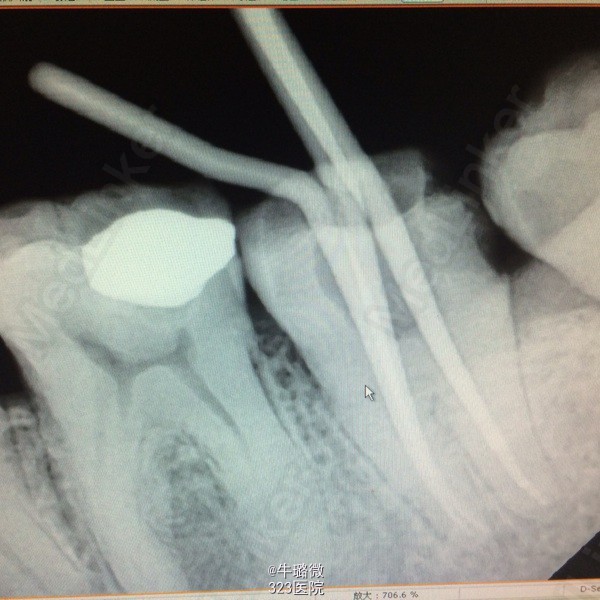

患者女42岁,左下后牙食物嵌塞痛数月余,近日夜间痛,要求治疗

左下8近中倾斜,左下7、8间食物嵌塞,左下7叩(+),探远中邻面(++)冷刺激敏感 x线片示:左下7远中邻面龋,远中髓角降低,龋坏至髓

诊断:左下7深龋致牙髓炎 建议:左下8拔除,左下7行RCT+桩+冠修复 处理:左下7降合,“必兰麻”下去龋,开髓,揭髓顶,探近颊、近舌、远中三根管,测根长分别为18、18、19mm,双氧水盐水交替冲洗,干燥,封木馏油,ZOE暂封